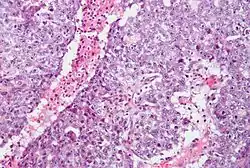

Nasieniak stanowi około 40–50% nowotworów germinalnych jądra u ludzi[88][89]. Makroskopowo zajęte przez nasieniak jądro jest powiększone, choć możliwe jest występowanie nowotworu w jądrze atroficznym[90]. Guz stanowi miękką masę o budowie jednorodnej lub drobnoguzkowej[91]. Powierzchnia przekroju jest koloru szarego, kremowego lub bladoróżowego. Mogą być obecne ogniska martwicy[90].

Mikroskopowo utkanie guza tworzą jednolite komórki nowotworowe ułożone w rozproszone arkusze, które mogą być dzielone przez cienkie przegrody łącznotkankowe na płaty. Okazjonalnie komórki układają się w kolumny albo gniazda[92]. Komórki nowotworowe są duże, mogą być okrągłe lub wieloboczne[91]. Zawierają umiarkowaną ilość eozynofilnej bladej cytoplazmy zawierającej glikogen oraz lipidy, jądra komórkowe są duże, okrągłe, zawierają jąderka, które mogą przybierać kształt pręcików, granice komórek są wyraźne[92][90]. Liczba mitoz jest zmienna, jednak zwykle jest wyraźna[90][92].

W obrębie przegród łączonotkankowych, a rzadziej pomiędzy komórkami nowotworowymi, obecny jest naciek złożony przede wszystkim z limfocytów, a czasem również z eozynofilów lub plazmocytów[90][92]. W 30–50% guzów obecna jest wyraźna reakcja ziarniniakowa[92][93]. Nowotwór powoduje zniszczenie prawidłowego miąższu jądra, który może być obecny na obwodzie zmiany[92].